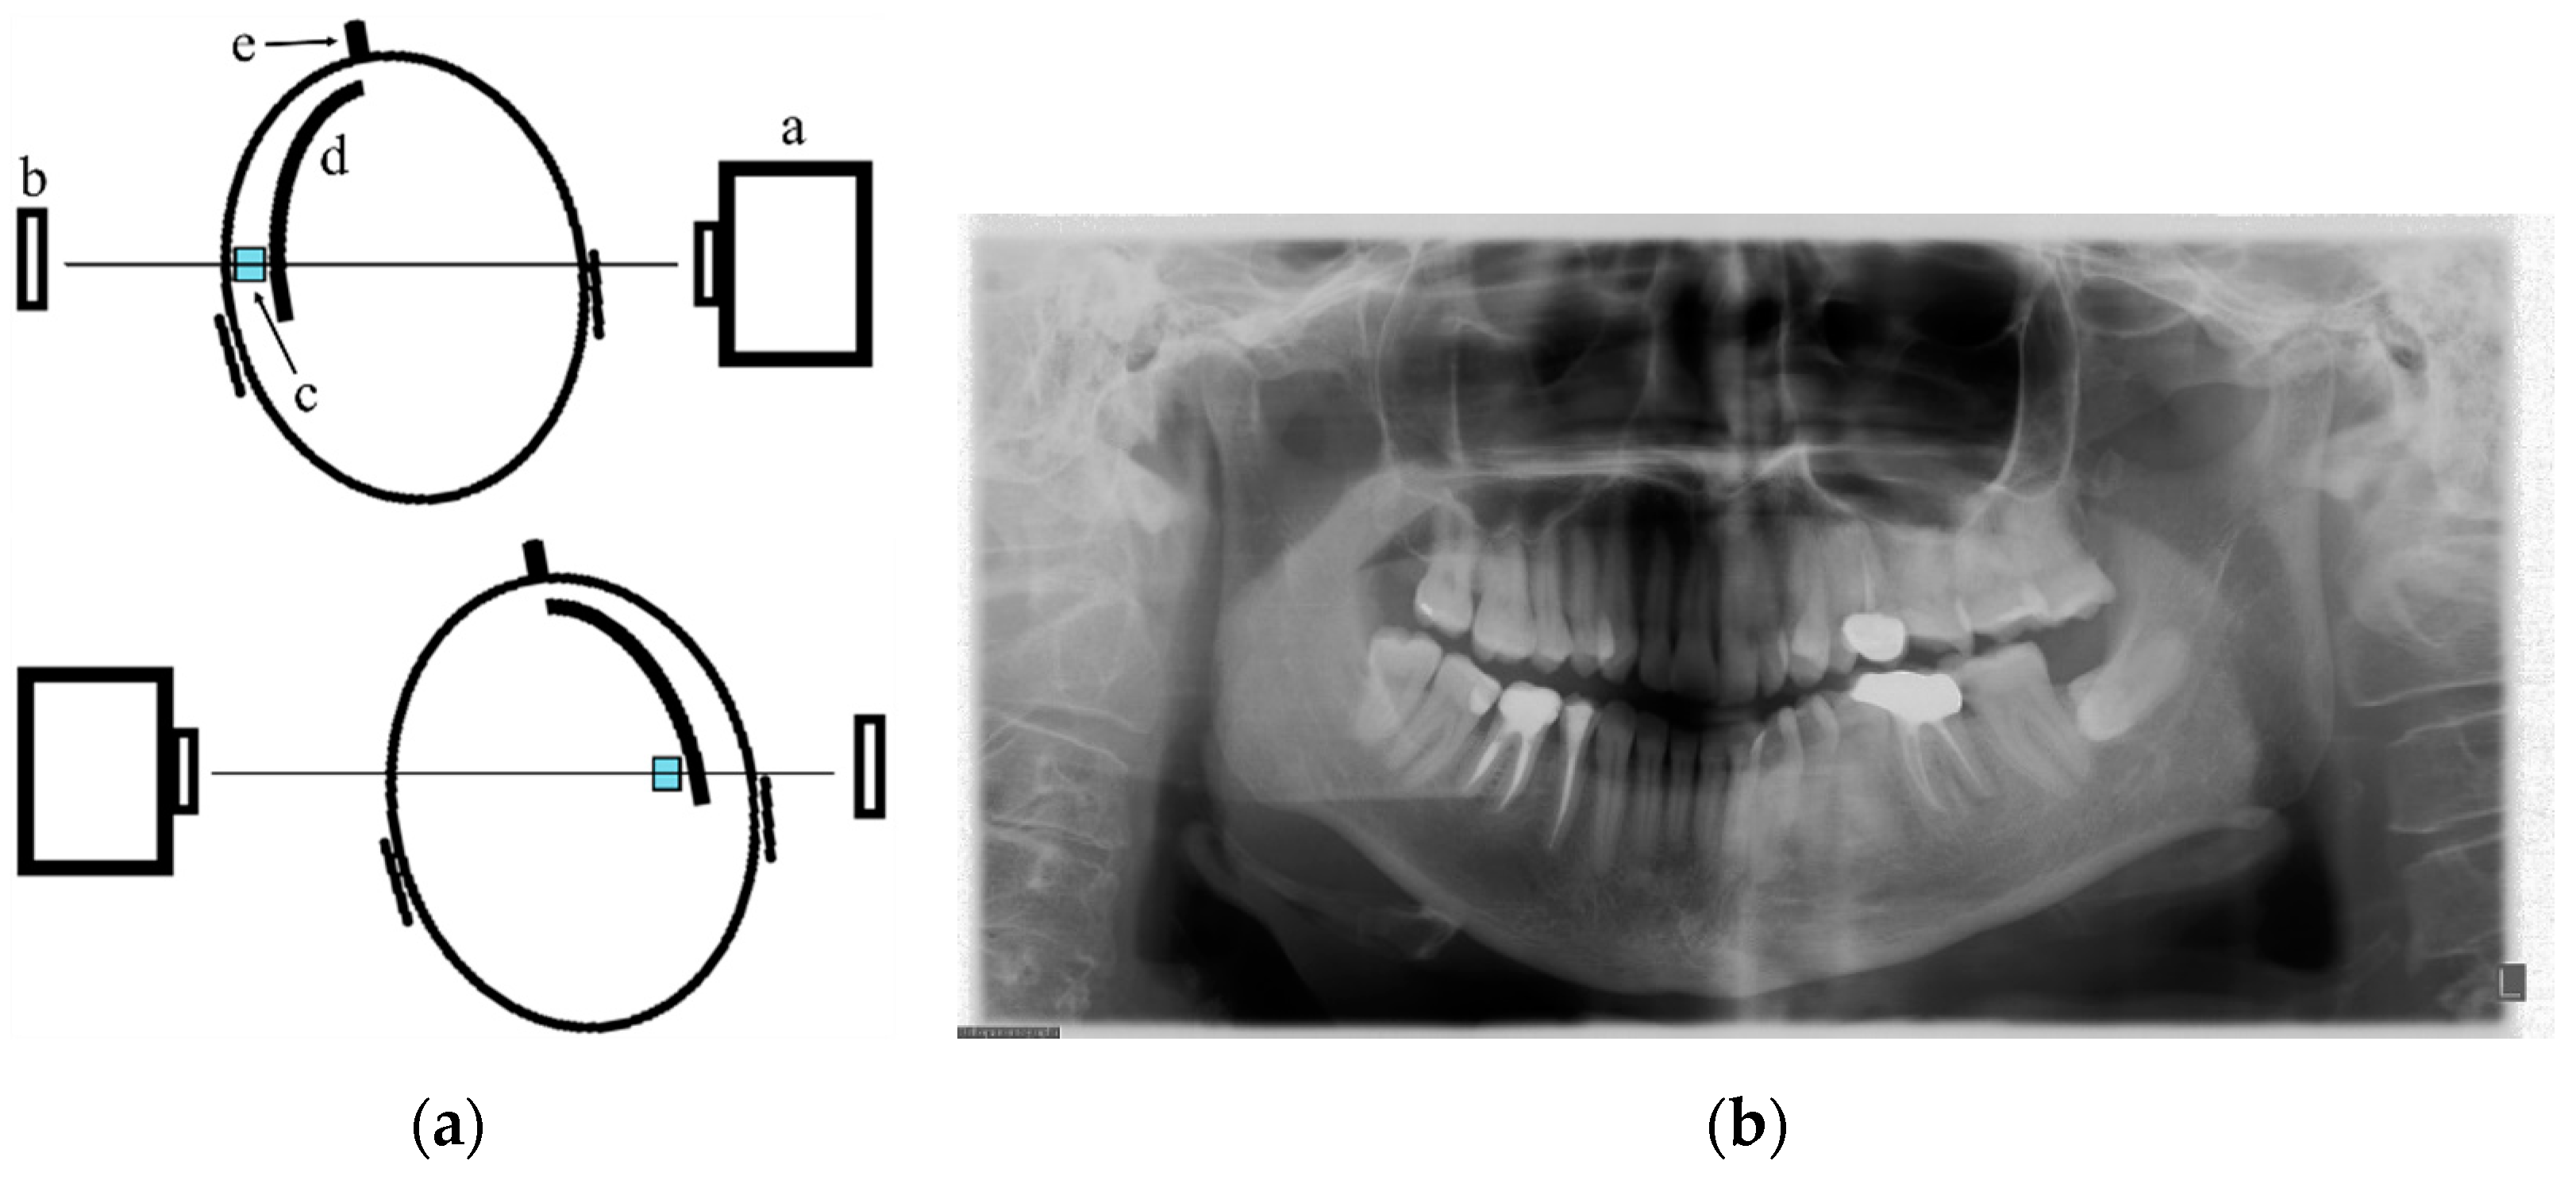

2. PAN Acquisition Principles